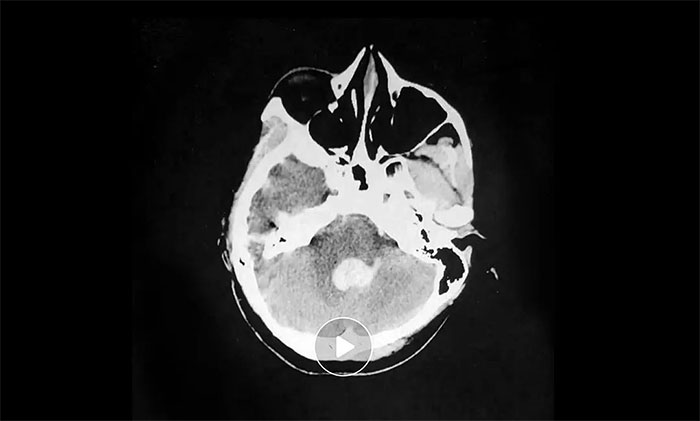

术后,在救治医院进行脑血管CTA检查发现:双侧大脑中动脉近端狭窄,左侧近乎闭塞,周围有异常血管网,诊断为“烟雾病”——这正是造成小雨突发脑出血的罪魁祸首。

“烟雾病”因颅底异常血管网在脑血管造影图像上形似“烟雾”而得名,危害极大,既可造成脑出血,也可发生脑梗死,更严重者可同时发生脑出血和缺血梗死。尤其当出血与缺血并存时,治疗过程将更为棘手。

▲ 异常血管网影像表现形似“烟雾”